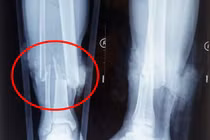

![]() |

| Phim chụp đoạn xương không có bàn tay phải. |